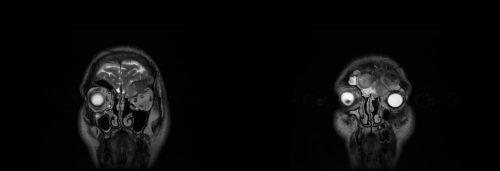

6. For this reason, he was submitted to a brain MRI for the evaluation of the extension of the mucocele and of the involvement of the frontal sinus posterior wall and the dura mater (Figures 2&3).

Figure 2 RM scan coronal view. The lesion reached the left supraorbital region with erosion of the roof of the ipsilateral orbit.

Figure 3 RM scan axial and sagittal view. The dura mater was not involved by mucocele.